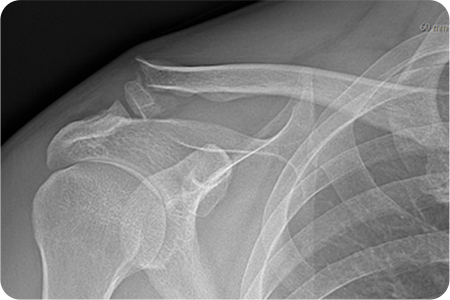

쇄골 골절 수술

쇄골 위쪽을 따라 약 5~8cm 정도 절개하여

골절 부위를 노출합니다. 정복과 고정을 시행하고

절개 부위를 봉합합니다. 수술 후 일정 기간 동안

팔의 움직임을 제한해 뼈가 안정적으로 붙도록 합니다.